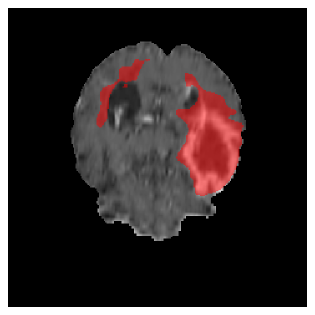

Appendix A Qualitative results

Figures 4 and 5 present the segmentation results for a patient from the BRATS dataset, visualized on a randomly selected slice. Figure 4 illustrates how tumor segmentation evolves over multiple episodes in S1 across different approaches including cumulative, naive, our approach, and the best buffer-free strategy (SI, =2). The cumulative approach, which trains on all encountered datasets together, maintains segmentation consistency across episodes but introduces significant amounts of false positives, particularly in the upper left area of the brain images. These misclassifications highlight its inability to generalize well across datasets despite access to all previous data. The naive approach, which learns sequentially without any continual learning strategy, suffers from severe catastrophic forgetting. While it initially segments well, performance deteriorates over episodes, leading to a near-complete loss of segmentation capability by the final episode. The SI (=2) approach, a regularization-based buffer-free CL strategy, performs reasonably well in early episodes but shows a significant performance decline over time. By the last episode, much of the tumor was no longer segmented, indicating difficulty in retaining prior knowledge. In contrast, our proposed approach initially produces more false positives but progressively refines its segmentation. By the final episode, it accurately retains the tumor region while minimizing misclassifications, demonstrating strong knowledge retention and adaptability across episodes. This suggests that our approach effectively mitigates catastrophic forgetting while maintaining segmentation performance over sequential learning.